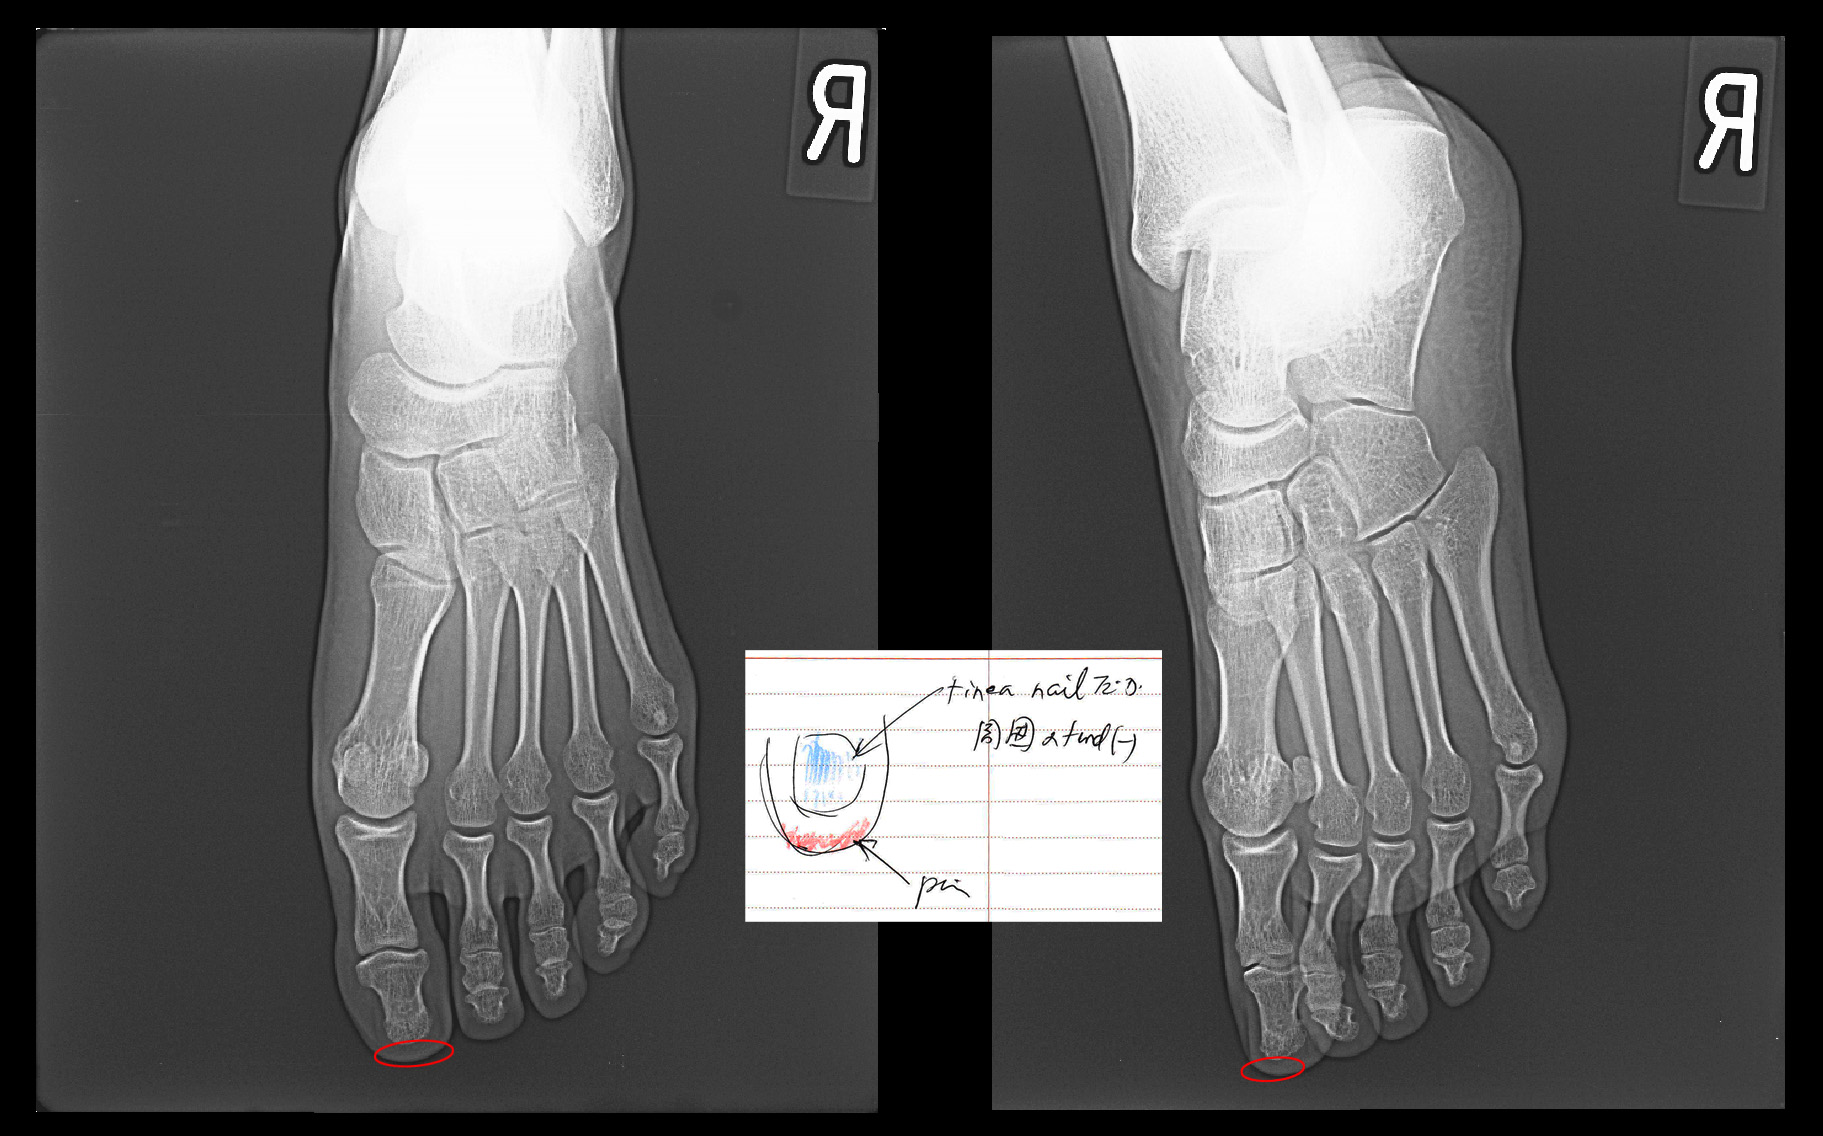

Kさんの足・足指のレントゲンは撮影しておらず、提示するレントゲン像は他の患者さんのものを代用していますが、中央にカルテに記載した図の赤領域が患者さんが針を刺すような痛みを訴えていた部位です。診断上重要なことは左第1足指の痛みの部位に圧痛を認めないということです。圧痛とは局所を押してみて痛みが確認されれば圧痛+で、その局所に痛みの原因があると医師は判断し、押してみて痛みが出なければ、その局所には痛みの原因がないと判断することが多いのです。この患者さんの痛みの領域はごく限定的な領域ですから、そこに痛みを起こす病態があれば必ず圧痛をともなうはずです。例えば巻き爪で爪が皮膚に食い込んで痛みを起こす場合がありますが、その場合には爪の周囲を押せば痛く、患者さんは押されるのを嫌がるものです。トゲが刺さって痛い場合も同様です。しかしKさんの足指には圧痛がないのですから、医師は左第1足指の足先には痛みの原因がないと判断するのです。では、痛みの原因はどこにあるのでしょうか。Kさんは足指の痛みとともに腰痛を訴えています。私は左第1足指の痛みは腰が原因で起きた坐骨神経痛の一症状だと判断しました。このようなことは時々あるものです。

次の患者さんは44才男性のSさんです。令和5年1月13日に当院を受診されました。数年前から右第1足指の内側に感覚の違和感があったとのことですが、最近指先に針で刺すような痛みが出てきたので受診したということでした。赤丸領域が違和感の部位で赤矢印が針刺すような痛みの部位です。

その時のMRI画像となりますが、圧迫骨折を発症した第1腰椎の右上の水平断では脊髄の軽度~中等度の圧迫の所見が確認できます(赤矢印)。第12胸椎(Th12)と第2腰椎(L2)高位での脊髄は円形または楕円形の形態です。第1腰椎での脊髄の圧迫が右第1足指の違和感の原因となってもおかしくはないと考えます。令和5年には腰椎MRI検査は行っていませんが、松飾りで受傷したKさんのように腰椎の下位レベルで加齢による椎間板ヘルニアが起きていて、第1腰椎の変形と椎間板ヘルニアの相乗効果で右第1足指の痛みとなっていたかもしれません。とにかく受傷後間もなくの数年前から右第1足指の違和感が続いていたわけですから、その違和感は第1腰椎の圧迫骨折とそれにともなう脊髄圧迫に起因しているという理解で良いのではないかと私は考えます。Sさんにとって右第1足指の痛み生活に支障があるほどではなく、長年気になっていたということの方が大きな問題であったのだと推察します。Sさんは私の説明に納得して、それ以上の検査や治療は希望されませんでした。